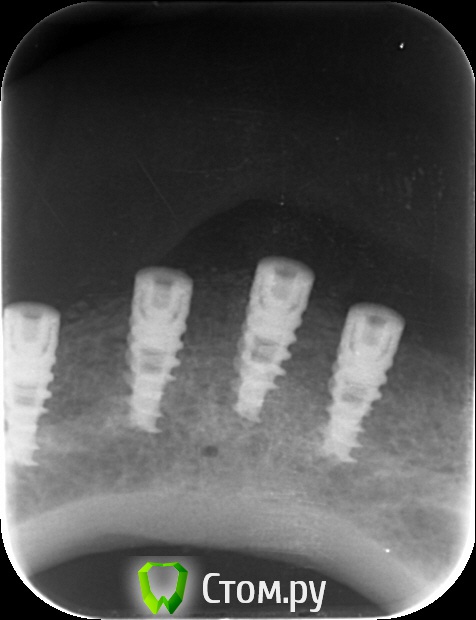

kriokov Опубликовано 1 октября, 2014 Поделиться Опубликовано 1 октября, 2014 (изменено) http://www.imageup.ru/img283/1894829/12.jpgставьте четыре, потом локаторы, если бюджет ограничен (про н\ч ведь разговор)К администраторам-- тему видимо во врачебный надо перенести Изменено 1 октября, 2014 пользователем kriokov Ссылка на комментарий

an_ver Опубликовано 4 октября, 2014 Поделиться Опубликовано 4 октября, 2014 Низ - 4 шт. в межментальном с немедленной нагрузкой.Согласен.Есть и у меня такая бабуля Ссылка на комментарий

an_ver Опубликовано 4 октября, 2014 Поделиться Опубликовано 4 октября, 2014 Бабуля уже год как с протезом бегает)) диаметр у бабули)) 3,75*10 мм, шаровые абатменты ТВ,сьемник армированный,верх такая же картина..4ь шт.+ТВ+сьемник армированный 2 Ссылка на комментарий